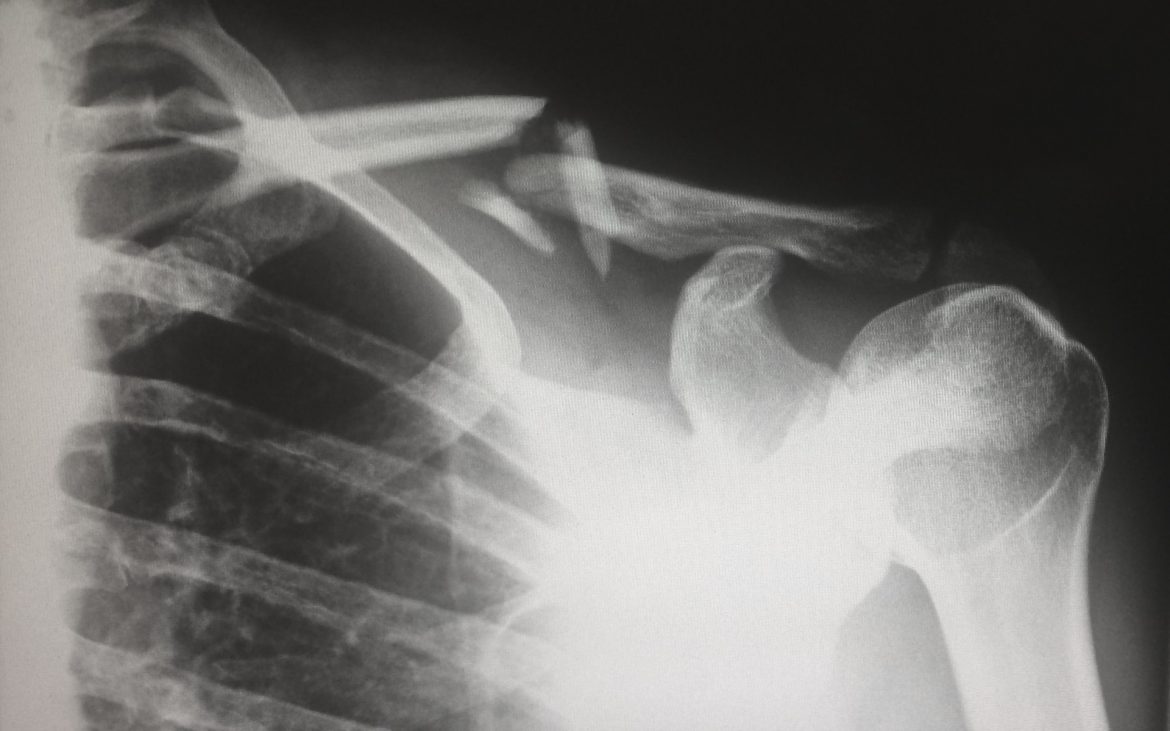

Osteoporosis is a condition where the bones become fragile due to decreased bone mass and bone tissue. The name itself translates to “porous bones”, indicating the hollow nature these bones acquire.

Our bones are dynamic structures, constantly undergoing processes of breakdown and regeneration. The balance between these processes ensures healthy bone density. However, in osteoporosis, this balance is disrupted, leading to increased bone breakdown and insufficient bone formation. The result? Bones that are more susceptible to fractures, even from minor impacts.

Many people remain unaware they have osteoporosis until a fracture occurs. However, bone density scans, commonly referred to as DEXA scans, provide an effective way to diagnose the condition early, enabling timely interventions.